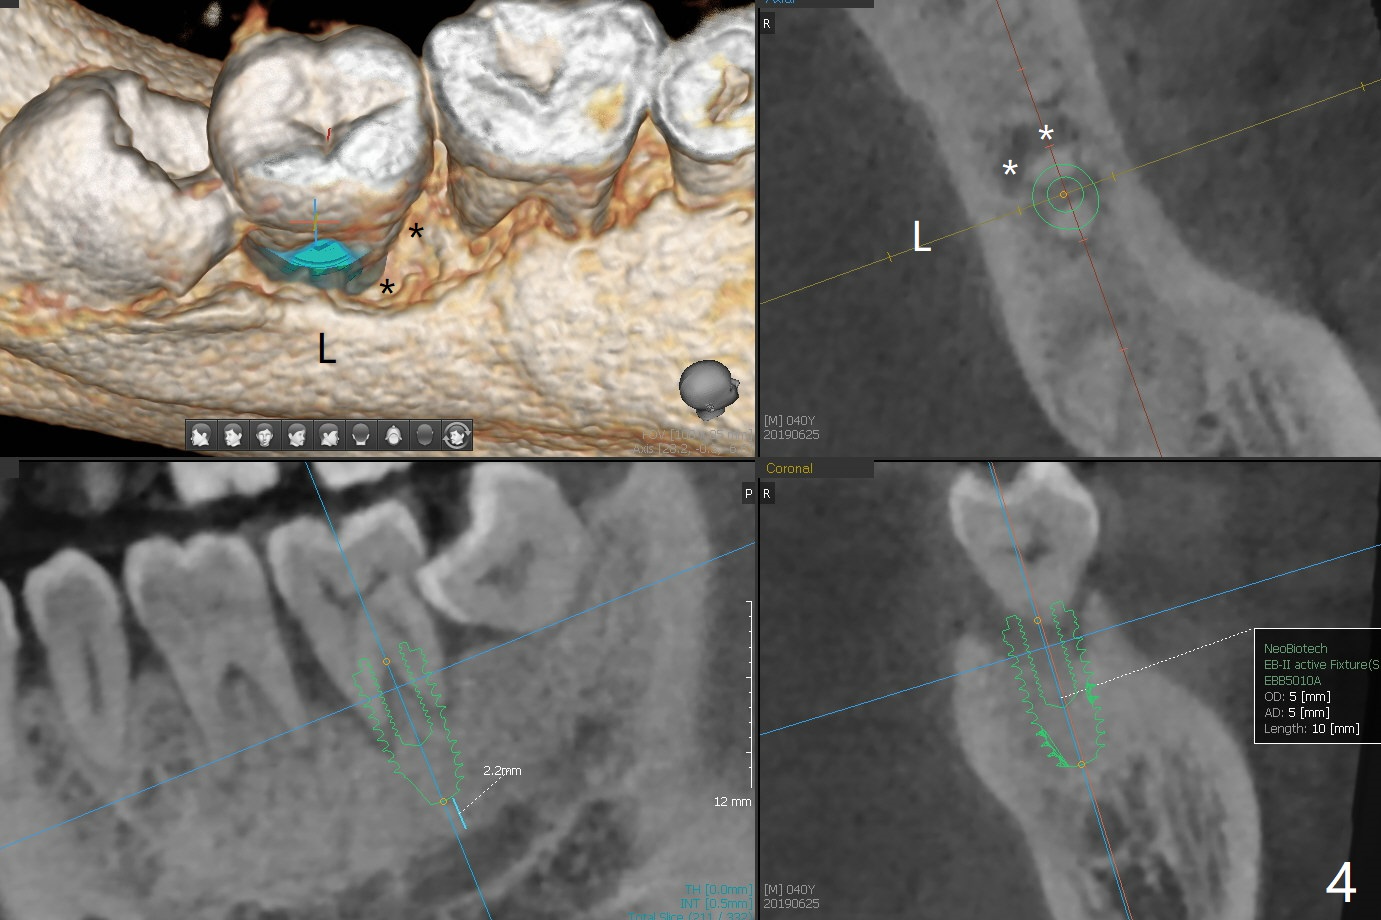

A 40-year-old man (smoker, 1ppd) is concerned about #31 mobility (Fig.1). Gross debridement is finished in his 1st appointment, while impression is taken for guide in his 2nd one. SRP has been scheduled for lower right quadrant with #31 extraction and immediate implant (Fig.2). The tooth #17 extraction will be postponed. The extraction may lead to mobility of the tooth #18, although SRP for the other 3 quadrant will be scheduled 1 week post #31 surgery. Smoke reduction is encouraged. When the crown is delivered at #31 one year later, the tooth #18 is loose (Fig.3) with lingual fistula. Since bone loss is more severe lingual (L *), a 5x10 mm immediate implant will be placed buccal (Fig.4). The tooth #17 will be kept as a distal stop for guide and extracted after #18 implant placement. Bone loss at #18 is more severe with mobility 15 months later; a shorter implant will be placed (Fig.5). After local scaling & root planing of the distal surface of #19 and application of Endogain, place sticky bone (red circle). Insert Collagen or Osteogen Plug in the #17 sockets.